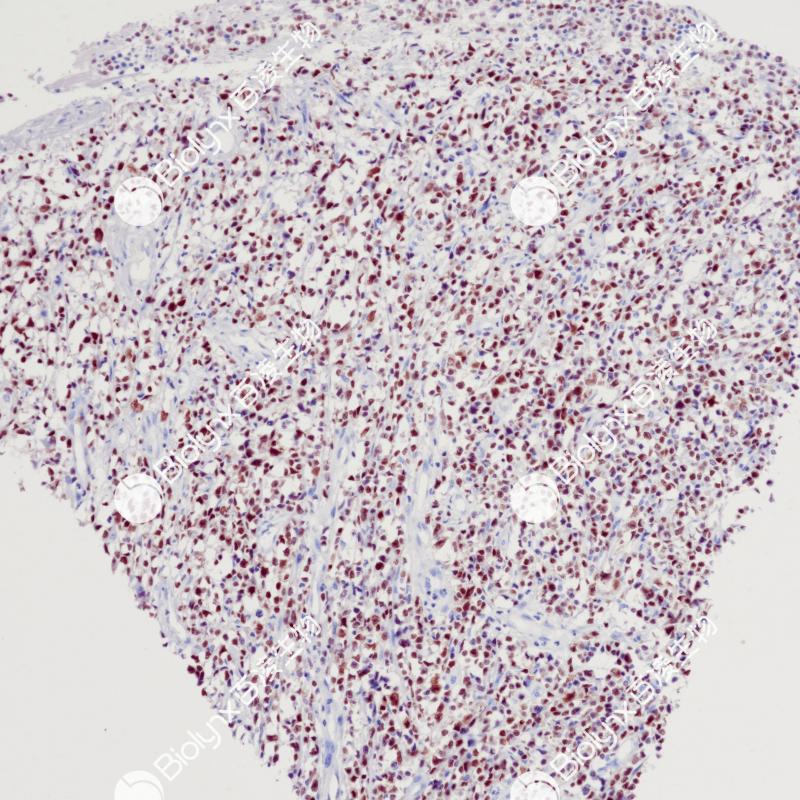

去分化脂肪肉瘤CDK4(BP6230)染色

细胞周期蛋白依赖性激酶4 (CDK4)是一种参与细胞周期的蛋白丝氨酸激酶。CDK4在高分化和去分化脂肪肉瘤中高表达,但在其他良性脂肪肉瘤和其他肉瘤中很少表达。CDK4联合MDM2可鉴别高分化脂肪肉瘤(+)、去分化脂肪肉瘤(+)和黏液样脂肪肉瘤、多形性脂肪肉瘤、梭形脂肪瘤等高级别肉瘤。

阳性对照

去分化脂肪肉瘤

亚细胞定位

细胞核